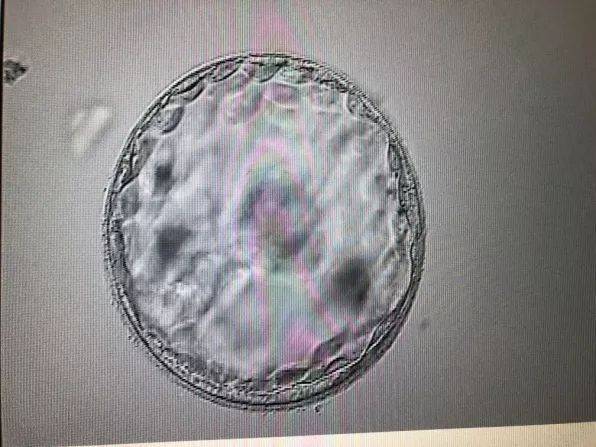

1. 存在胚胎:彩超图像中可以看到一个明显的胚胎结构,通常表现为一个圆形或椭圆形的暗影,这是胎儿的原始形态。

2. 胚胎发育:胚胎内部可以看到明显的胎心搏动,这是判断胚胎是否存活的重要指标。

3. 宫内妊娠:胚胎位于宫腔内,与宫壁相贴,而非异位妊娠。